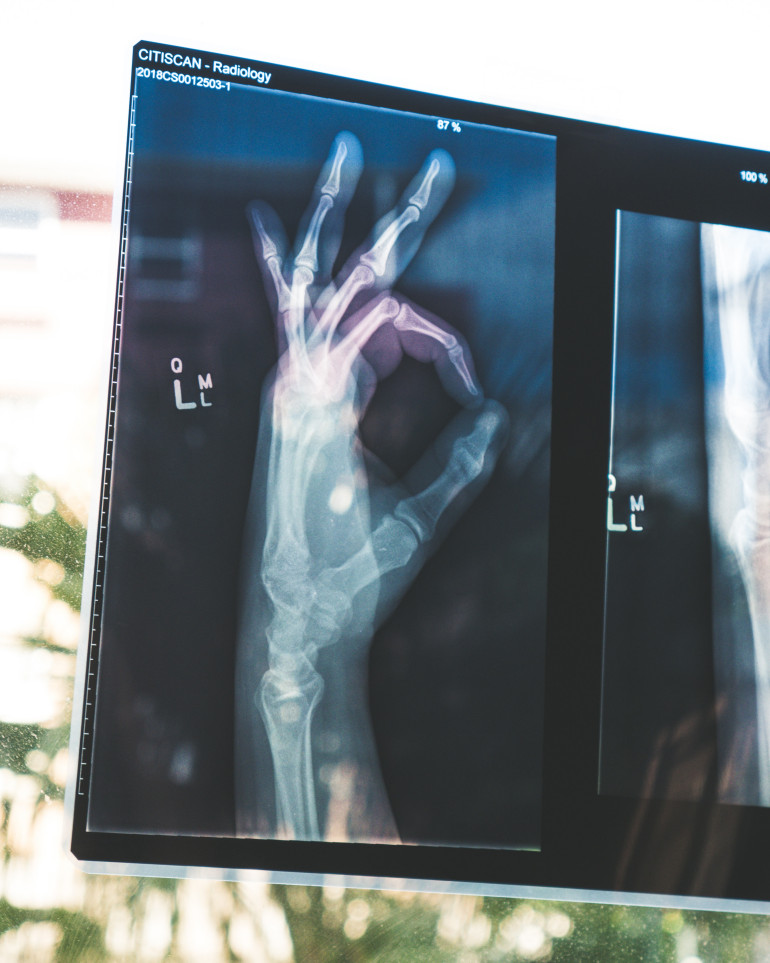

Biomateriał regenerujący tkankę kostną

Naukowcy opracowali nowy biomateriał umożliwiający kościom szybsze gojenie się dzięki poprawie zdolności regeneracyjnych komórek macierzystych u dorosłych.

Badanie zostało przeprowadzone przez naukowców z RCSI University of Medicine and Health Sciences (Dublin) oraz szpital uniwersytecki CHI at Temple Street. Już wcześniej odkryto cząsteczkę o nazwie JNK3 – kluczowy czynnik zwiększający wrażliwość komórek macierzystych u dzieci i zapewniający lepszą regenerację kości niż u osób dorosłych.

Odkrycie to pozwala przynajmniej częściowo wyjaśnić, dlaczego kości dzieci goją się szybciej. Opierając się na uzyskanej wiedzy, badacze stworzyli biomateriał naśladujący strukturę tkanki kostnej i zawierający nanocząsteczki aktywujące JNK3. Testy przedkliniczne wykazały, że biomateriał ten przyczynia się do szybkiej regeneracji znacznych ubytków kostnych i ogranicza stan zapalny.